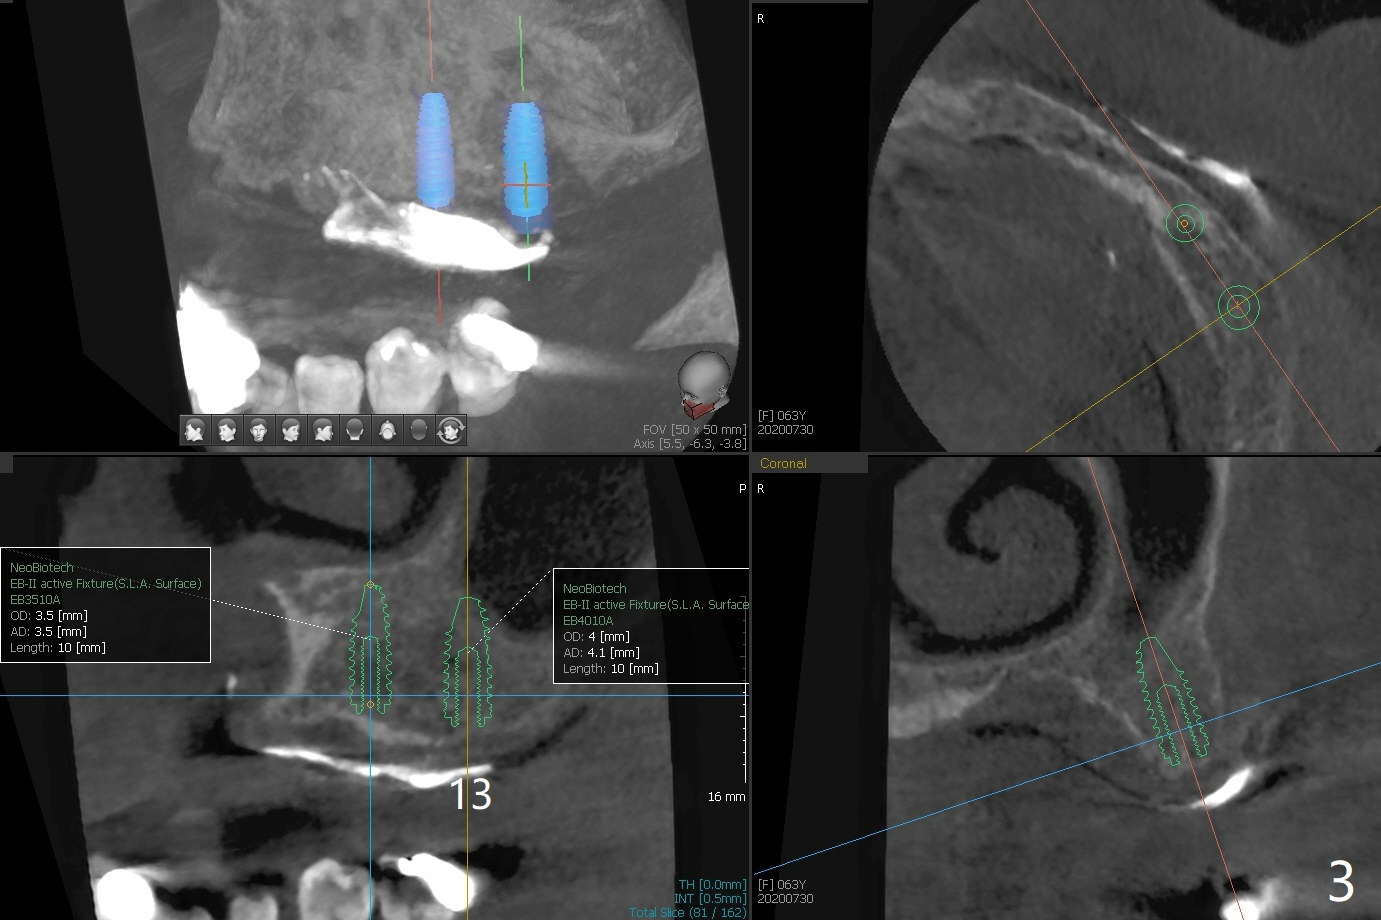

A 63-year-old woman presents to clinic with fractured crown/post at #26 (Fig.1). After recementation of the crown, the upper Valplast RPD is found to be unstable. After discussion, she agrees to have two implants and ball abutments at #11 and 13 for retention. Use pink acrylic to fixate a denture tooth of #3 to the Valplast. Alginate impression (upper and lower jaws with RPDs and upper without RPD) will be taken to make radiographic stent (Barium Sulfate). With the latter, take small field CT (5x5 cm) to decide the size of the implants. After implant and ball abutment placement, soft reline the Valplast until osteointegration. When Barium Sulfate and Jet are mixed with monomer, the mixture is applied to tissue surface of #11-13 of the upper Valplast. CT is taken. The latter shows that the bone at #11 is thin, while the bone at #14 is short. The sites of #12 and 13 are proper for implant placement (Fig.2,3).